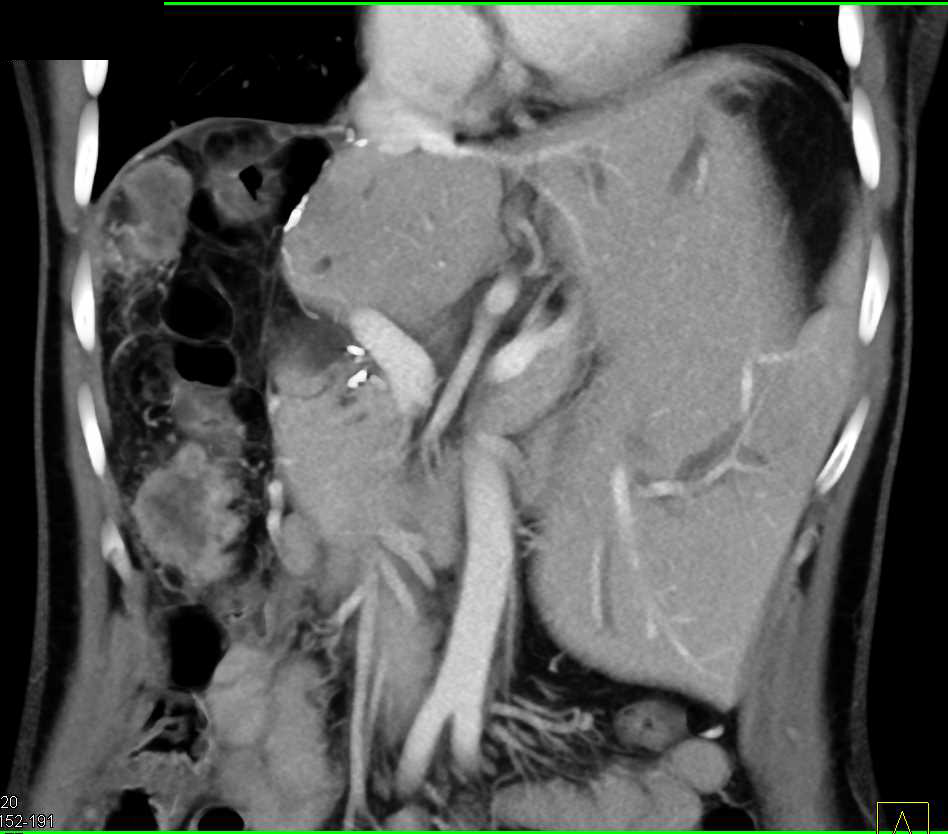

GSW with Multiple Sites of Bleeding Including Right Cervical Region and Liver